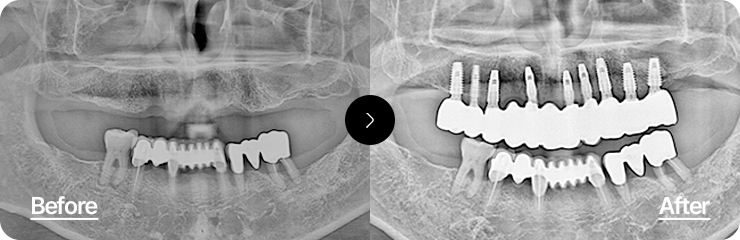

상실된 치아 전체를 복원하여

자연스럽고 건강한 구강 기능 회복

최소한의 임플란트로 최적의 위치에 식립하여 기능과 심미성을 동시에 회복하는 치료입니다.

정확한 교합 분석과 풍부한 임상 경험이 요구되는 고난이도 시술입니다.